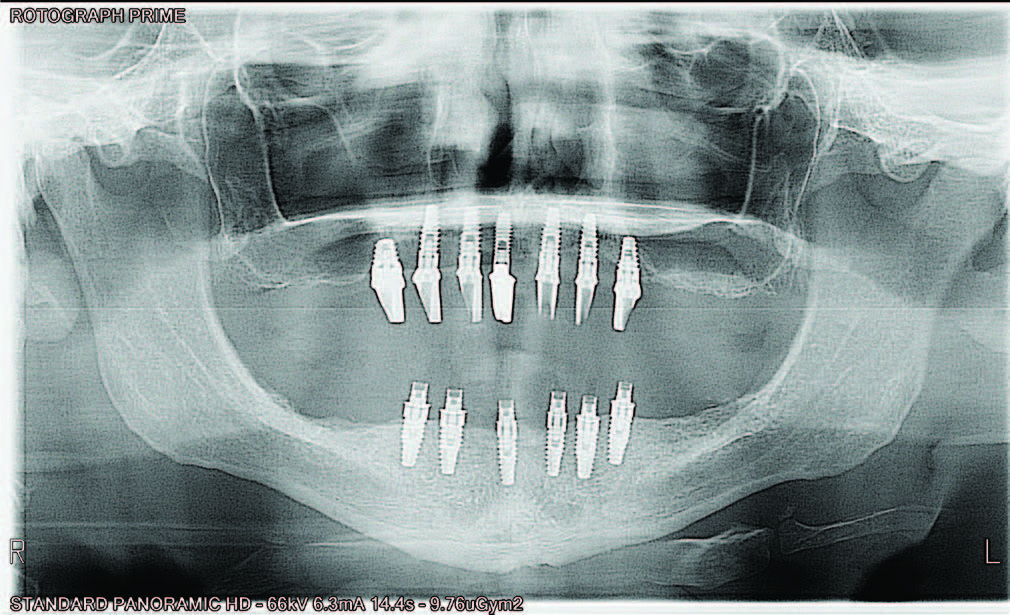

The retracted view and the patient’s full-face smile are demonstrative of the excellent laboratory communication and careful attention to each step in this patient’s journey (Figures 20 and 21). His oral care required extra attention due to his emotional and psychological deficits caused by his hydrocephaly. While dentists cannot guarantee the longevity of prostheses, the journey from this patient’s beginning to his new oral restorative beginning creates hope and changes interpersonal feelings and responsibility. The implant placement and number should allow for optimal mastication throughout his life with proper maintenance and homecare (Figure 22).